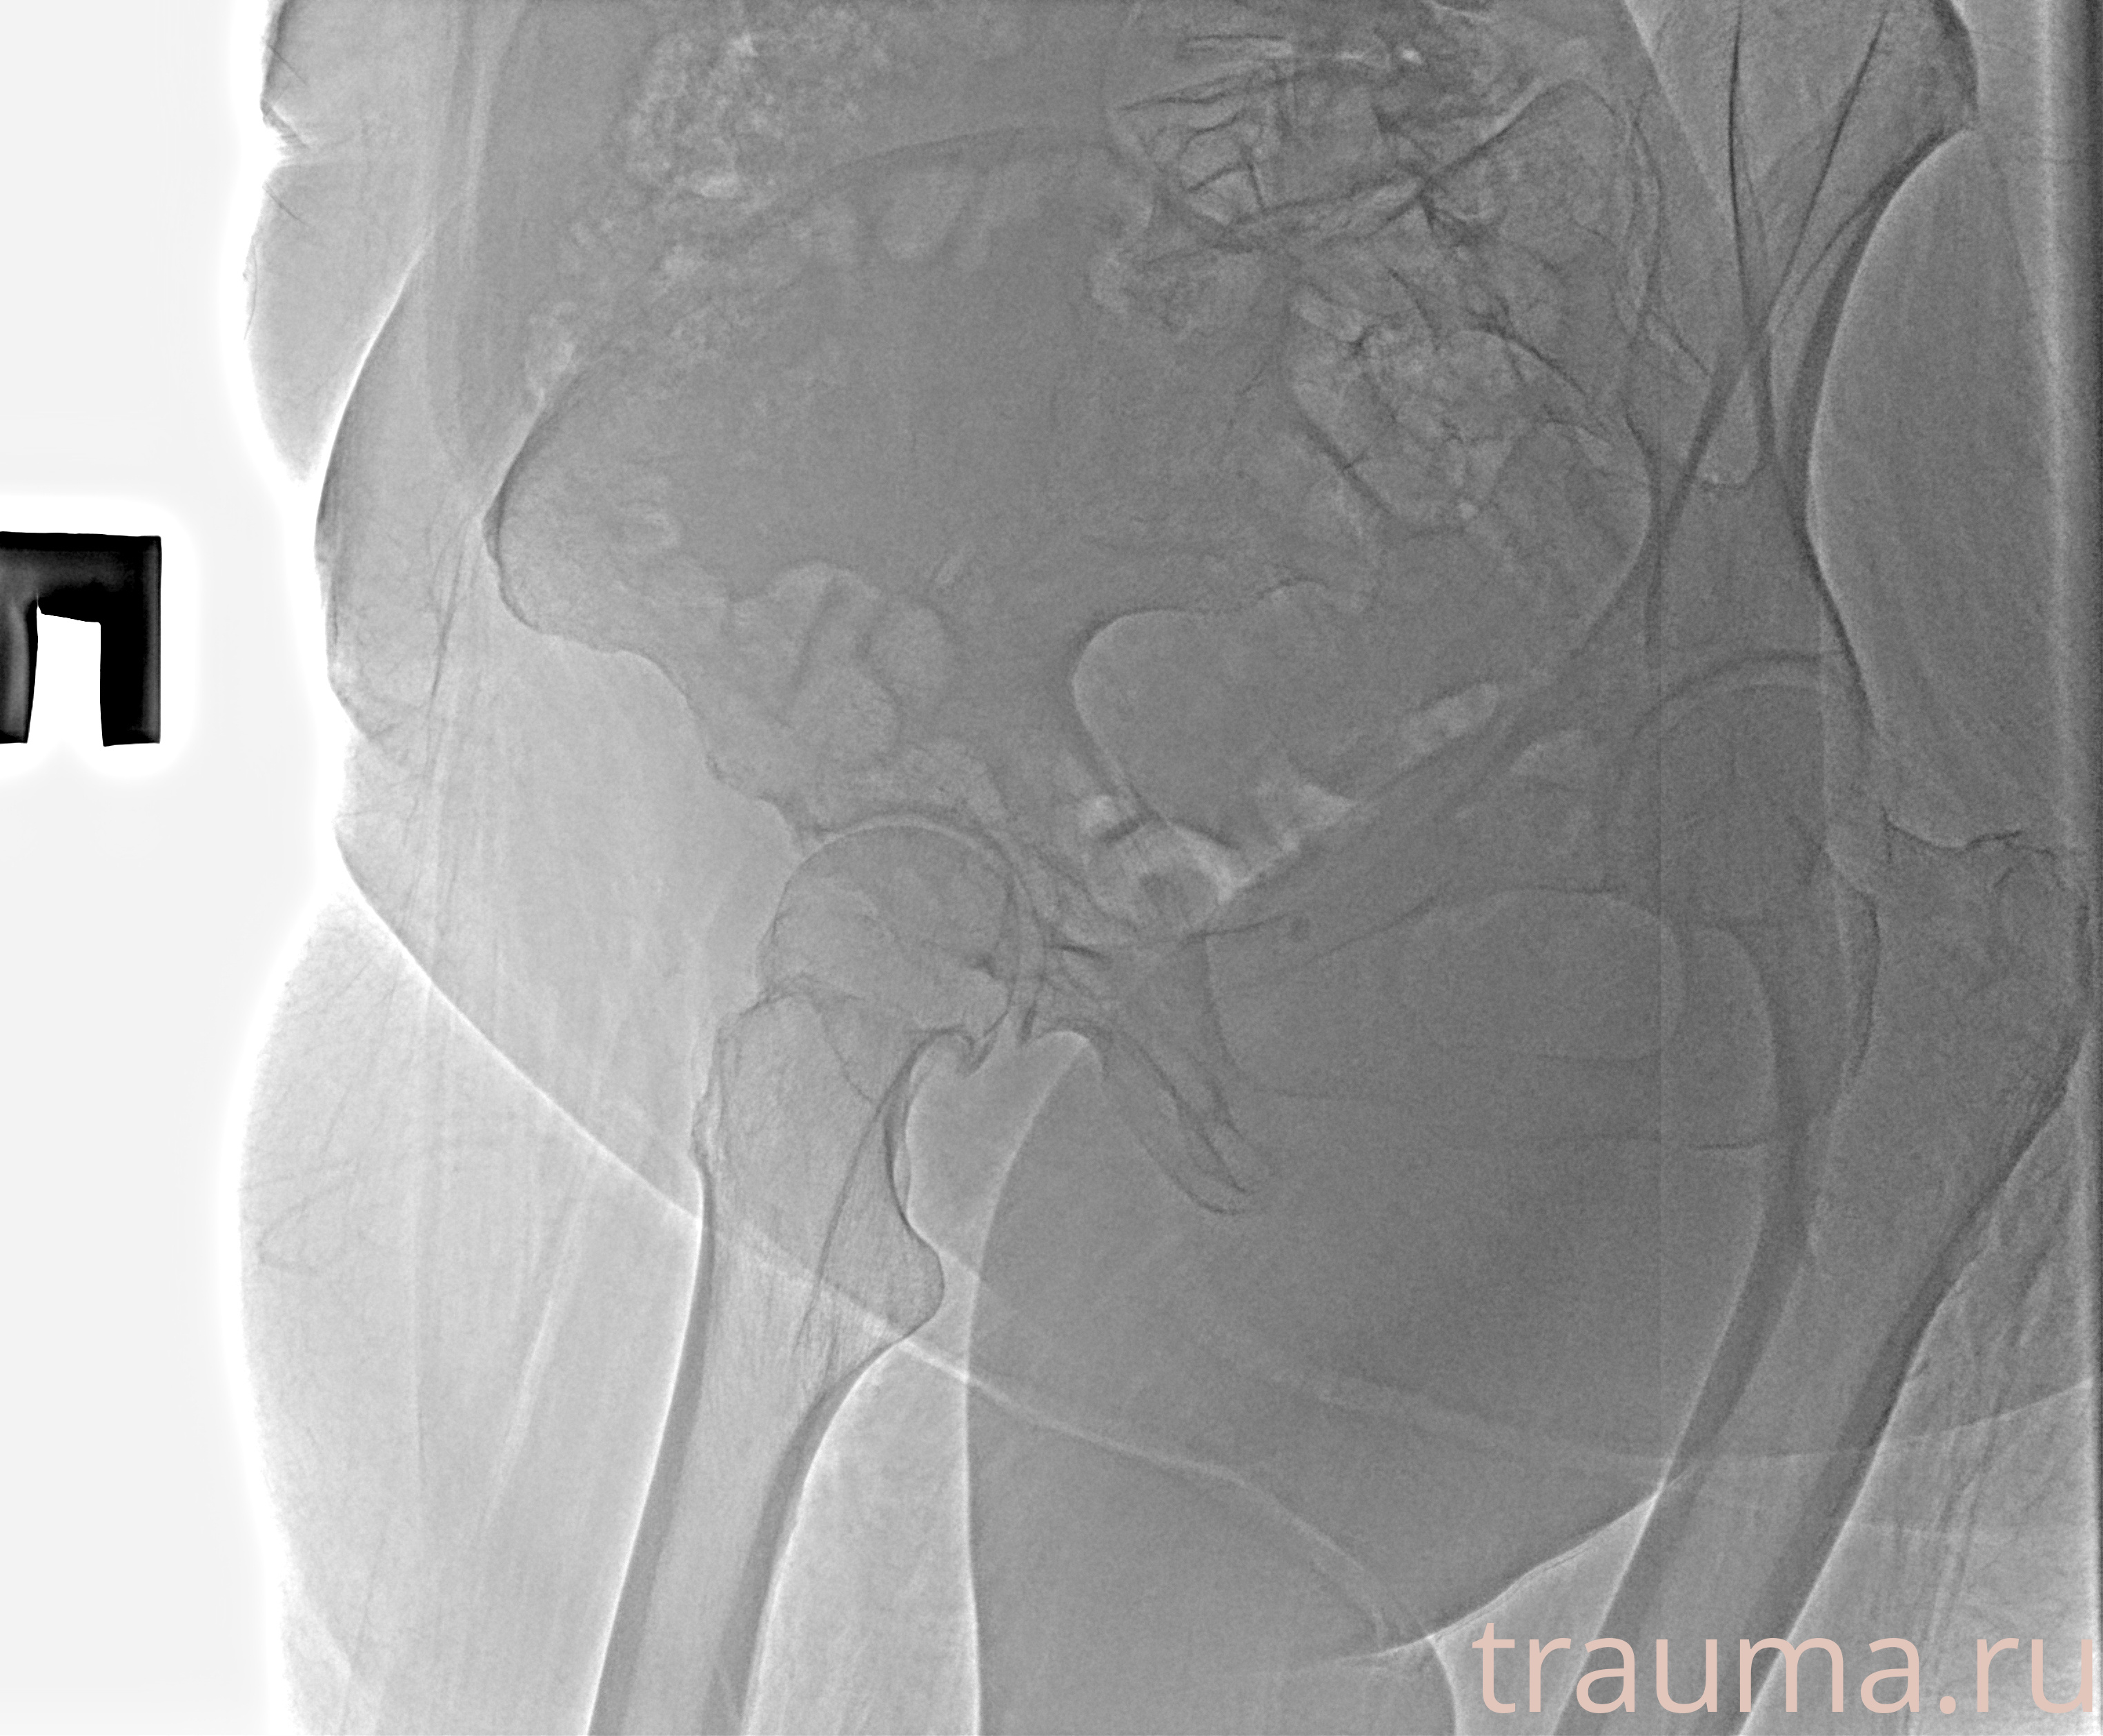

Рентгенограммы

Рентген на дому: по вашему адресу приезжает врач-рентгенолог, травматолог-ортопед с мобильным рентгеновским аппаратом, проводит диагностику травмы или заболевания, делает необходимые рентгенограммы, дает рекомендации по дальнейшему лечению. Получить качественные снимки в домашних условиях возможно благодаря уникальной методике, разработанной МосРентген Центром для института  Склифосовского